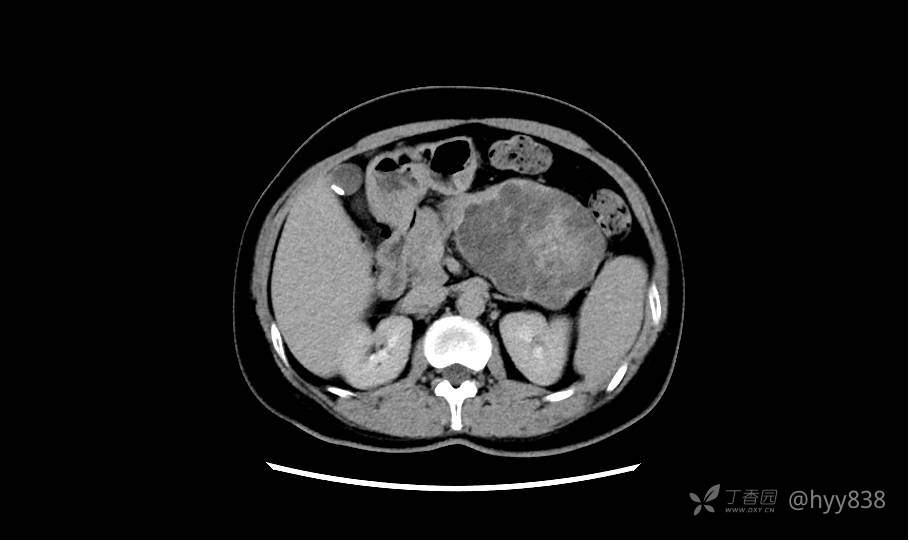

胰腺增强动脉期